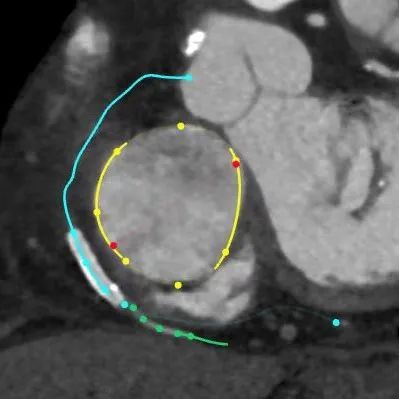

术前CTA

经过术前分析,患者的手术具有很大的挑战。不仅有曾经开胸手术史,右冠的整个后瓣环区有一个支架,给手术带来了很大的难度。经过潘湘斌教授心脏团队的讨论,决定在后瓣靠近隔瓣的位置,植入K-Clip®,进行后隔瓣环的缩环成形,以期改善反流。